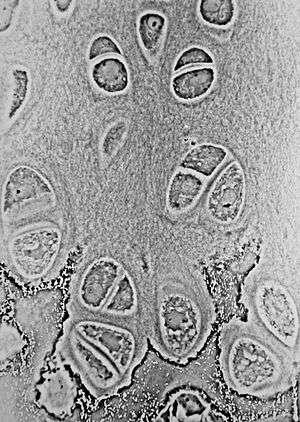

Histology

The growth plate has a very specific morphology in having a zonal arrangement.

| Epiphyseal plate zone (from epiphysis to diaphysis | Description |

|---|---|

| Zone of reserve | Quiescent chondrocytes are found at the epiphyseal end |

| Zone of proliferation | Chondrocytes undergo rapid mitosis under influence of growth hormone |

| Zone of maturation and hypertrophy | Chondrocytes stop mitosis, and begin to hypertrophy by accumulating glycogen, lipids, and alkaline phosphatase |

| Zone of calcification | Chondrocytes undergo apoptosis. Cartilagenous matrix begins to calcify. |

| Zone of ossification | Osteoclasts and osteoblasts from the diaphyseal side break down the calcified cartilage and replace with mineralized bone tissue. |